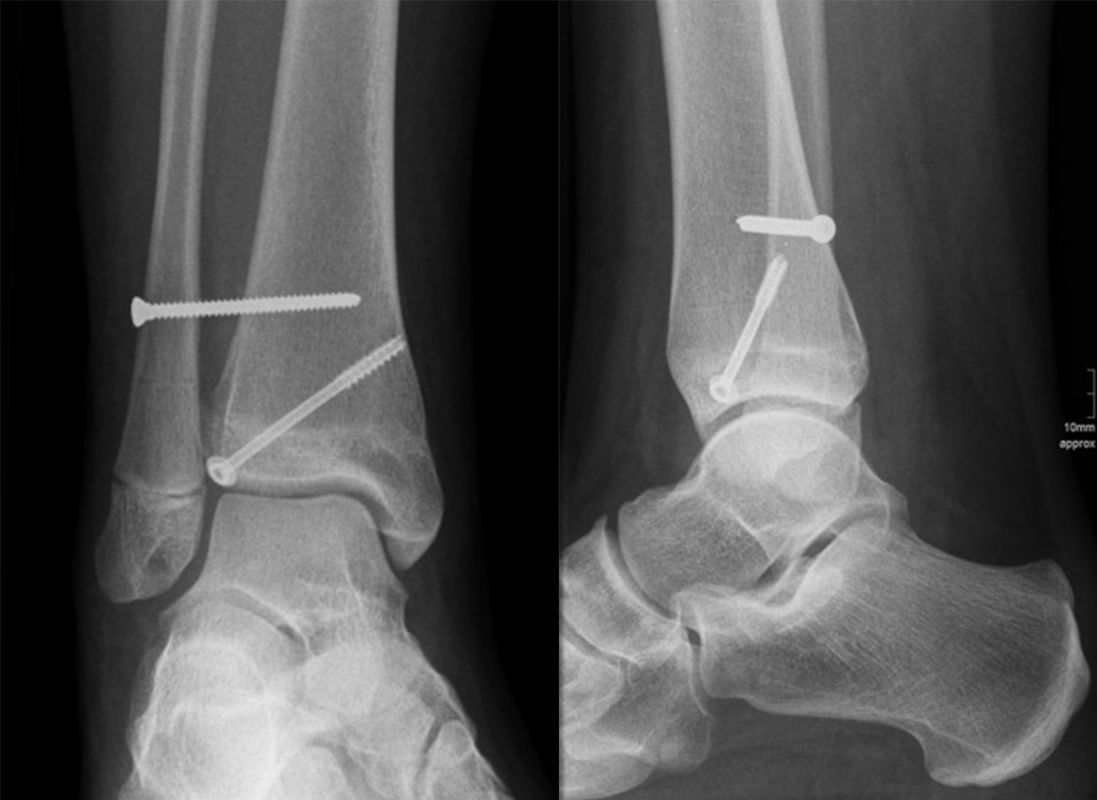

Übergangsfrakturen

Übergangsfrakturen sind spezielle Verletzungen, die ausschließlich in der Lebensphase beobachtet werden, in welcher die Wachstumsfugen teilweise geschlossen sind. Die Wachstumsfuge an der distalen Tibia schließt sich von ventromedial beginnend nach dorsal und lateral. Während die bereits geschlossene Wachstumsfuge eine hohe Stabilität aufweist, ist der knorpelige Anteil der noch offenen Fuge wesentlich weniger widerstandsfähig. Die mechanisch schwächste Schicht der Wachstumsfuge ist der Blasenknorpel. Durch Biege- und Scherkräfte kommt es zu einer Verletzung der Wachstumsfuge mit Aussprengung eines metaphysären Keils. Übergangsfrakturen sind „unvollendete“ Fugenschaftfrakturen bei welchen die bereits geschlossene Fuge ein Auslaufen der Frakturlinie durch die Fuge verhindert und daher die Bruchlinie ins Gelenk ausläuft (v. Laer 2013).

Rein epiphysäre Frakturen werden als Twoplane-Frakturen bezeichnet. Der Frakturverlauf liegt in der Epiphyse und dem noch nicht verknöcherten Anteil der Wachstumsfuge. Gibt es noch einen zusätzlichen metaphysären Keil handelt es sich um eine Triplane-Fraktur. Bei einer Triplane-Fraktur kann sich in Einzelfällen die metaphysäre Fraktur bis in die Epiphyse fortsetzen, sodass eine zusätzliche Querfraktur resultiert. Es entsteht der Eindruck eines zusätzlichen hinteren Volkmann Fragments.

• Twoplane-Fraktur: Epiphysäre Fraktur, welche epiphysär und durch den noch nicht verknöcherten Teil der Fuge verläuft (Aitken II Verletzung bei einer teilweise mineralisiert Wachstumsfuge).

• Triplane-I-Fraktur: Epiphysäre Fraktur, mit teilweisem Verlauf durch die Wachstumsfuge und gleichzeitigem metaphysären Keil.

• Triplane-II-Fraktur: Epiphysäre Fraktur, mit Verlauf durch die Wachstumsfuge. Der metaphysäre Keil setzt sich in die Epiphyse fort, was zu einer weiteren quer verlaufenden Frakturlinie im Gelenk führt.

In Abhängigkeit vom Reifezustand der Wachstumsfuge kann der epiphysäre Frakturspalt sehr weit medial bis ganz lateral zu liegen kommen. Ein sehr weit lateral liegender Frakturspalt entspricht funktionell nahezu einem knöchernen Ausriss der vorderen Syndesmose, was sich im Röntgenbild an einer erweiterten Malleolengabel erkennen lässt 9

Der teilweise komplexe Frakturverlauf bei Übergangsfrakturen lässt sich im CT zuverlässig darstellen 10. Der erfahrene Untersucher kann bereits mit Röntgenaufnahmen des Sprunggelenks in zwei Ebenen in Verbindung mit zwei 45° Schrägaufnahmen sehr umfassende Aussagen zum Frakturverlauf treffen (v. Laer 2013), die Präzision und Aussagekraft der Computertomografie ist aber zweifelsohne überlegen und wird von den meisten Behandlern bevorzugt 11, auch wenn sich zu diesem Thema in der Literatur eine teilweise sehr emotional geführte Diskussion findet. Einigkeit hinsichtlich der Indikation für ein Schnittbildverfahren besteht bei Triplane-Frakturen, wenn Zweifel darüber bestehen, inwieweit die metaphysäre Fraktur den tragenden Gelenkanteil tangiert 12.

THERAPIE

Übergangsfrakturen weisen häufig nur eine geringe Dislokation auf (Abb. 25). Möglicherweise wurden diese Verletzungen in ihrer Rolle hinsichtlich einer Arthroseentwicklung lange Zeit überbewertet 13. Nicht dislozierte Frakturen können konservativ behandelt werden.

Dislozierte Frakturen (Frakturspalt > 2 mm) werden grundsätzlich operativ behandelt. Die Reposition kann arthroskopisch unterstützt erfolgen. Die Schraubenosteosynthese erfolgt entsprechend dem Frakturverlauf. Bei Twoplain Frakturen ist meist eine epiphysäre Schraube ausreichend die von lateral kommend das Fragment nach medial-proximal fixiert. Der Schraubenverlauf ist üblicherweise von lateral ventral nach proximal dorsal medial (Abb. 24). Nach Reposition darf in der seitlichen Aufnahme des Sprunggelenks, als auch in der 45° Außenrotationsaufnahme keine Stufe in Höhe der Wachstumsfuge erkennbar sein. Eine sichtbare Stufe ist Indikator für eine unzureichende Reposition.

Bei Triplane-Frakturen fasst die metaphysäre Schraube das metaphysäre Fragment einschließlich eines hinteren Volkmann Dreiecks, die epiphysäre Schraube fasst das epiphysäre Fragment. Da der Fugenschluss noch nicht abgeschlossen ist, sollten die Schrauben die Wachstumsfuge nicht kreuzen, obwohl eine Wachstumsstörung unwahrscheinlich ist (v. Laer 2013).

Die Nachbehandlung umfasst eine sechswöchige Entlastung im Gips. Nach Gipsabnahme wird die Bewegung freigegeben und eine schmerzadaptierte Aufbelastung erlaubt. Ein Sportbeginn ist normalerweise nach 10-12 Wochen möglich. Die Schraubenentfernung erfolgt nach 3-6 Monaten. Klinische Kontrollen nach sechs und zwölf Monaten erlauben ein frühzeitiges Erkennen von möglichen postoperativen Fehlentwicklungen. Sobald die Wachstumsfuge vollständig verschlossen ist, sind keine weiteren Kontrollen mehr notwendig.